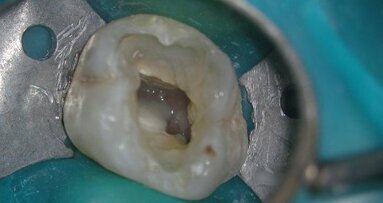

Endodontic treatment of teeth with significant coronal destruction is a very common clinical procedure in the restorative clinical practice. When we are ...